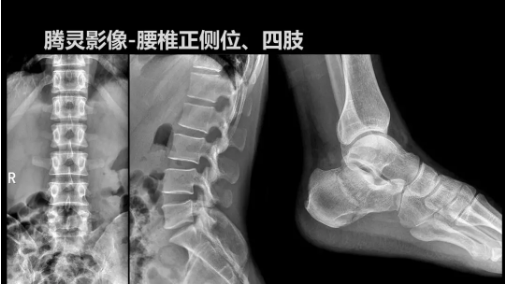

“騰靈”是安健科技的第四代動態(tài)DR產(chǎn)品,可實現(xiàn)全科室應用。如各類常規(guī)的X線檢查、消化道檢查、骨科檢查、婦科、兒科檢查等。此外,安健科技為“騰靈”在真正意義上實現(xiàn)多科室、多功能診斷進行了多項針對性設計。

其中包括SID范圍可調節(jié)能夠滿足多種類攝影要求、球管角度可調節(jié)能夠滿足不同投照部位的需求、超低床體設計方便患者上、下床、360°可旋轉腳踏板降低擺位難度、可移除式濾線柵能夠滿足兒科等特定場景的計量要求、可升降操控臺方便醫(yī)生床旁操作等,并配置了全身拼接功能,最大程度上適配動態(tài)DR產(chǎn)品的特點。

相較前代產(chǎn)品,“騰靈”在圖像質量方面得到了全面升級,“騰靈”采用17*17非晶硅平板探測器設計,采集矩陣達3072*3072,動態(tài)范圍達16bit,為成像提供超大視野的同時保證成像質量,此外,該款機型可根據(jù)醫(yī)療機構的差異化需求而選配不同的動態(tài)平板探測器,以此來適應不同階層用戶所需。